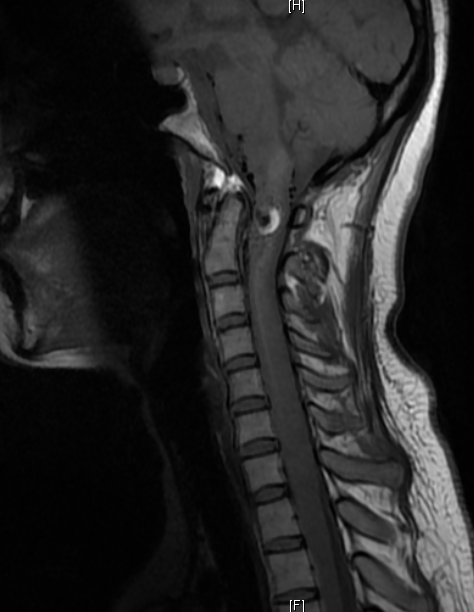

图1:术前MRI提示延髓高颈髓异常出血信号影(蓝色箭头指示)

神经外科王贵怀主任经过认真仔细的评估后,决定进行血肿清除和畸形血管切除术,再造脊髓髓内的血流。术后由神经外科神经介入专家苏伟医师给予复查血管造影,显示畸形血管基本全切,症状明显好转,住院2周已能下地自主活动,姑娘愁苦的脸上终于露出了笑容。